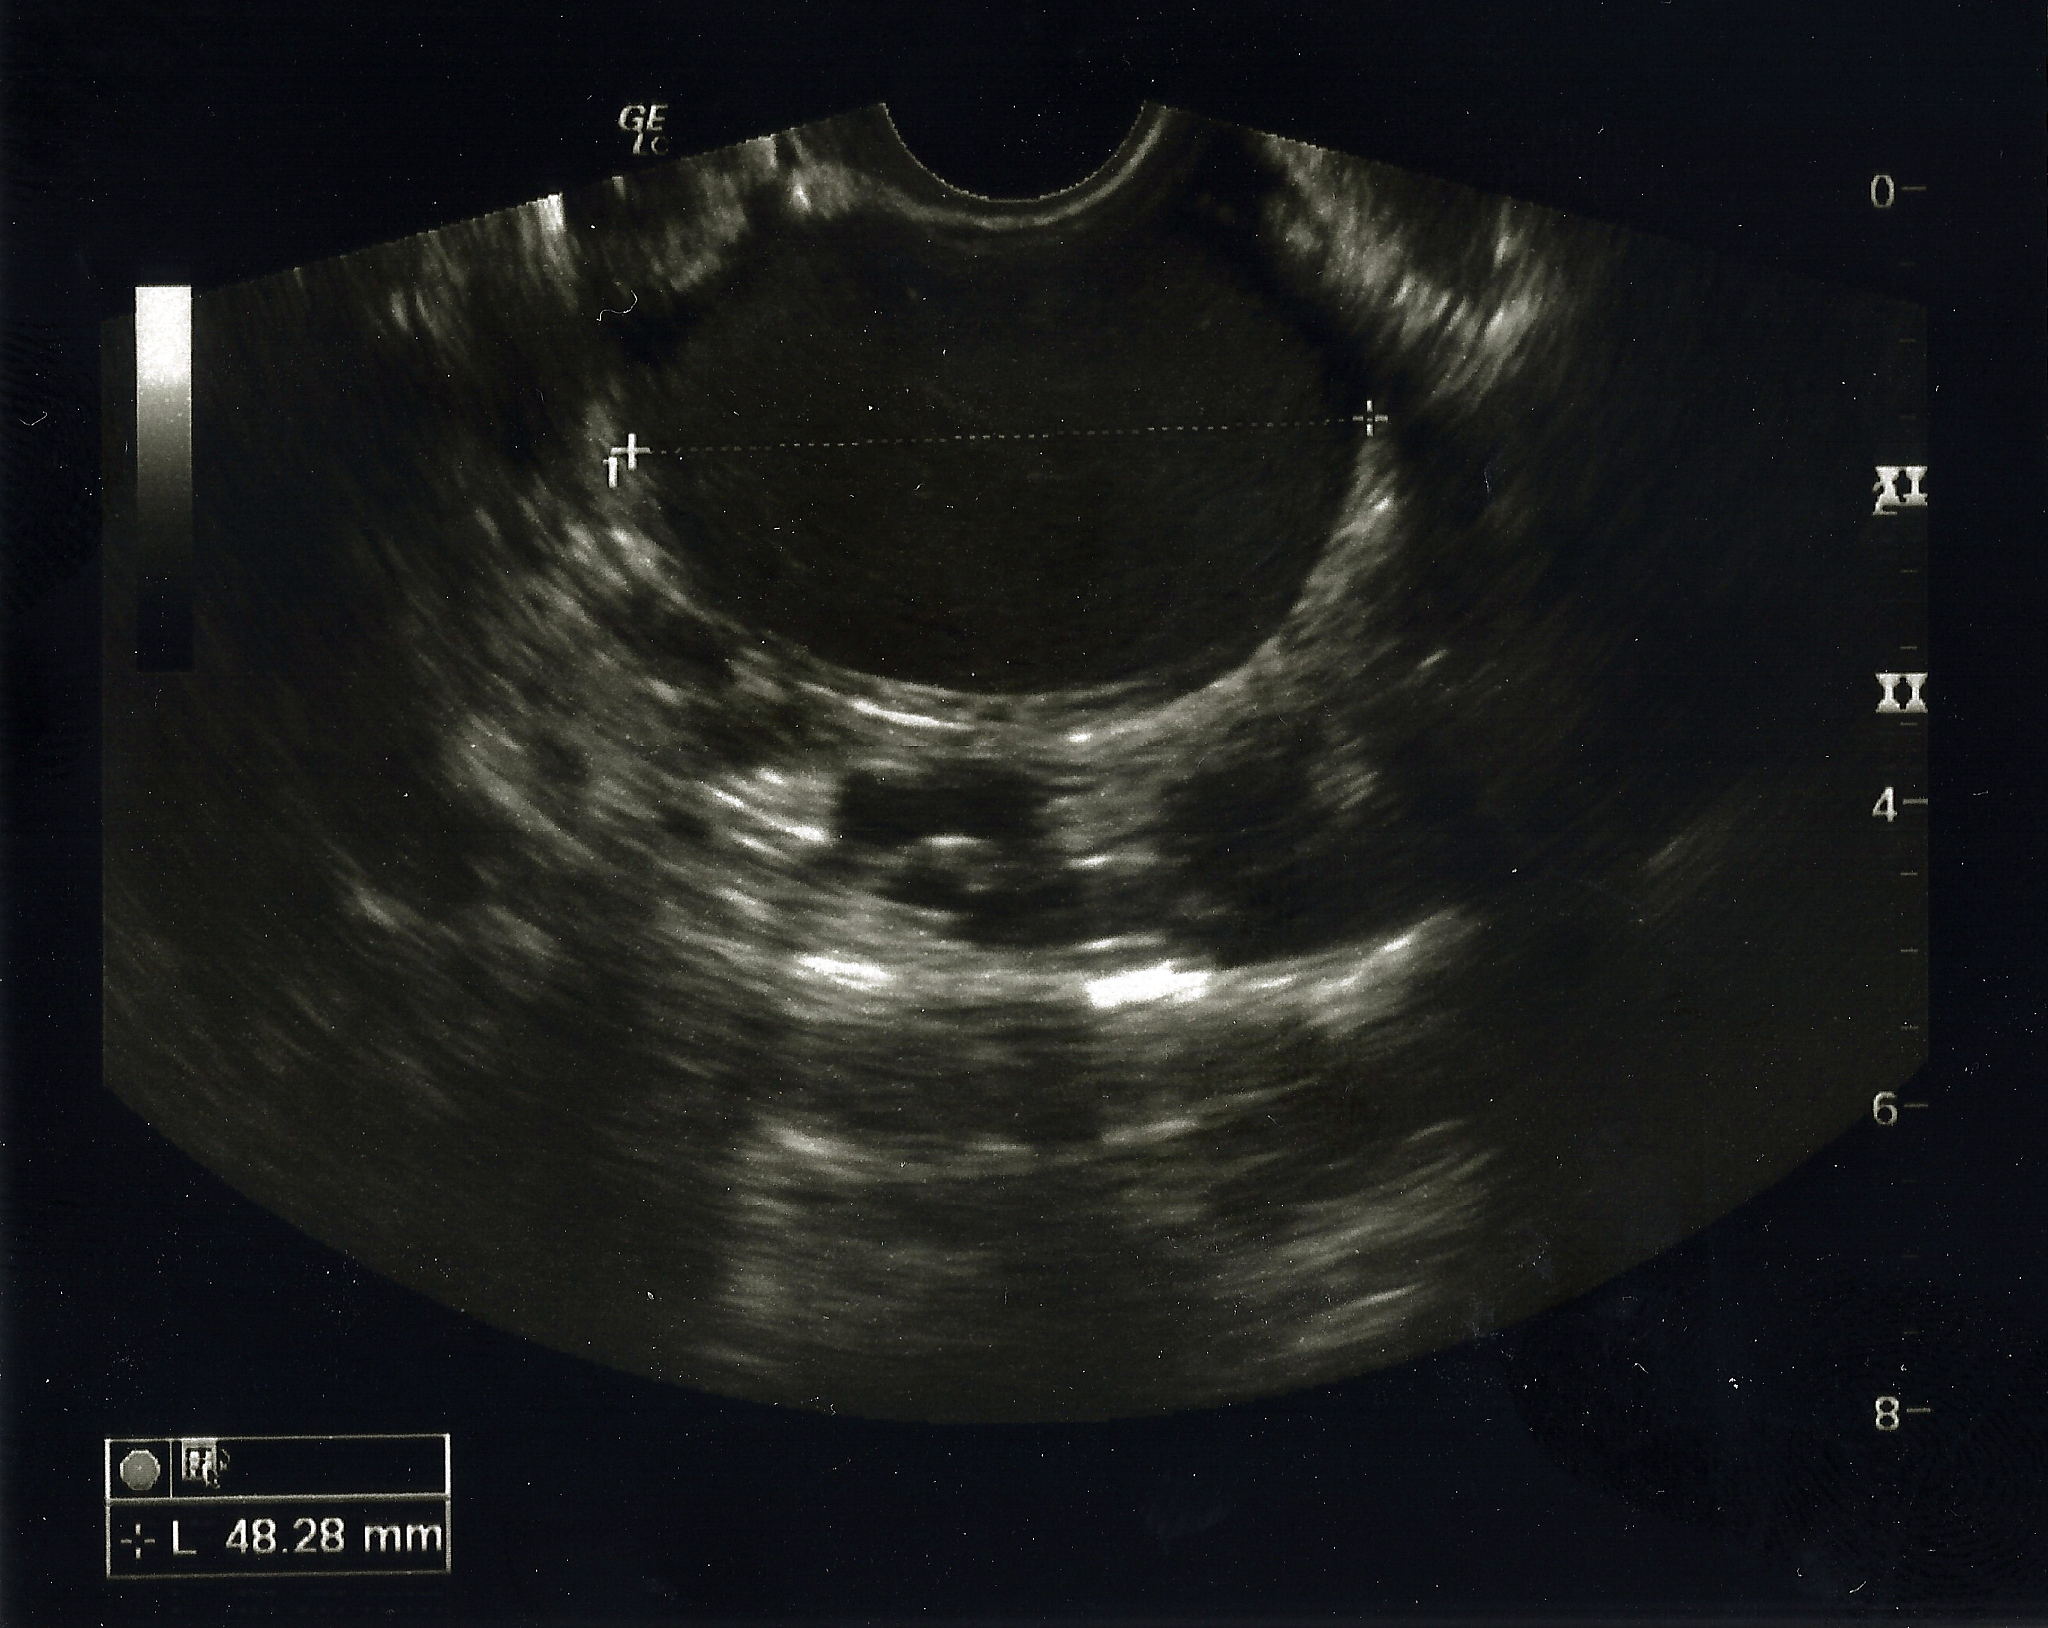

卵巢子宫内膜异位囊肿 (Ovarian Endometrioma) 是一种常见的妇科疾病,其流行病学和致病原因尚不完全清楚。以下是目前已知的一些情况:

1. 流行病学:卵巢子宫内膜异位囊肿主要发生在生育年龄的妇女中,尤其是 30-40 岁之间。据估计,大约有 5-10% 的妇女患有卵巢子宫内膜异位囊肿。